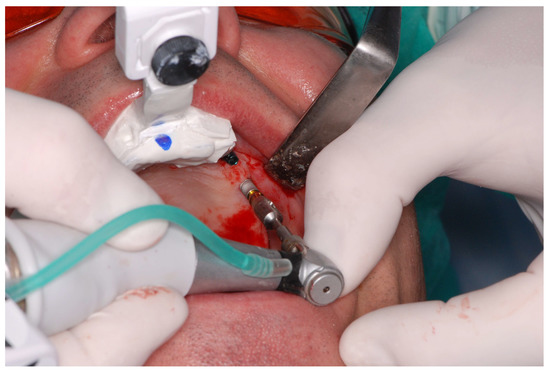

The surgical procedures were performed using the Navident dynamic navigation system shown in Figure 1 (Navident, ClaroNav, Toronto, ON, Canada). The surgeries were planned and performed using pre-treatment CBCT assessment. Immediately prior to the procedure, 3–6 landmarks (such as teeth, implants, bone edge or bone screws) were selected and registered to the patient using a dedicated mapping tool (tracer tool) equipped with an optical marker (head tracker).

The implant placement procedure was performed by a team of two dental surgeons with over 20 years of clinical experience. The procedures were performed under local infiltration anesthesia and block anesthesia using 4% articaine as anesthetic. The implant bed preparation was performed using a flapless approach. Each of the rotary instruments, including the punch, was calibrated and detected by the navigation system before being introduced into the surgical field, as shown in Figure 2.The drilling sequence for the Camlog implant system was used for the surgery, while the implant placement protocol was followed. The implants, as well as the surgical instruments, were calibrated and inserted under navigation guidance. The procedure was completed by securing the implant body with a locking screw, there was no need to suture a wound-Figure 3.

Figure 1. The dynamic navigation system in use—a surgeon performing a flapless implantation.